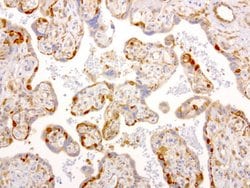

NME1 Mouse anti-Canine, Human, Rat, Clone: UMAB94, liquid, UltraMAB™

NME1 was identified because of its reduced mRNA transcript levels in highly metastatic cells. Nucleoside diphosphate kinase (NDK) exists as a hexamer composed of ′A′ (encoded by this gene) and ′B′ (encoded by NME2) isoforms. Mutations in the gene have been identified in aggressive neuroblastomas. Two transcript variants encoding different isoforms have been found for this gene. Co-transcription of this gene and the neighboring downstream gene (NME2) generates naturally-occurring transcripts (NME1-NME2), which encodes a fusion protein comprised of sequence sharing identity with each individual gene product.Specifications

| Immunocytochemistry, Immunofluorescence, Immunohistochemistry (Paraffin) | |